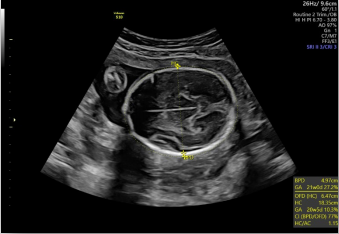

生長指標(biāo)半自動(dòng)測量

在合適切面下,可自動(dòng)識(shí)別測量臨床所需的胎兒雙頂徑,頭圍,腹圍,股骨長和肱骨長度等多個(gè)參數(shù)。